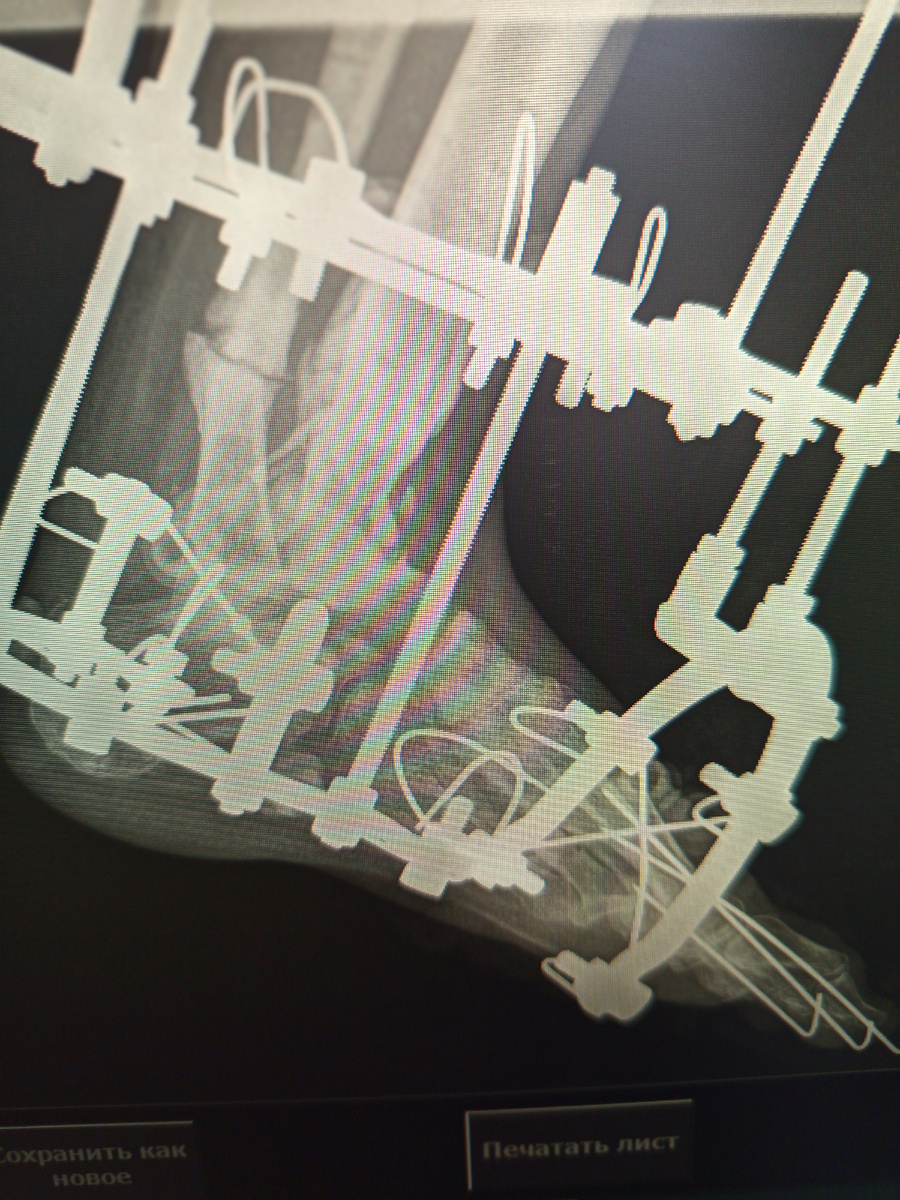

–Да тут вообще капец, "Илизар" ¹,еще что-то , наверное, а надо снимок стопы.

1. Илизар–аппарат Илизарова, внешней фиксации.

Ага , вижу интересную конструкцию , но , проблема в том , что пациентку привезли после операции , на контрольный снимок.

То , что нам мешает, то –нам поможет.

–Илизарова то у вас почему?

–Аа , да это уже полгода так, это у меня травма была.

А снимок и правда интересный

Ой , нет прямой проекции , почему -то строго боковая ((( Но , я ее переделала , строго боковая там не нужна, это Люба наснимала , пока я шла)

Поставили пациентке спицы. Режим при установленных металлоконструкциях нужно давать побольше , они на себя много забирают.